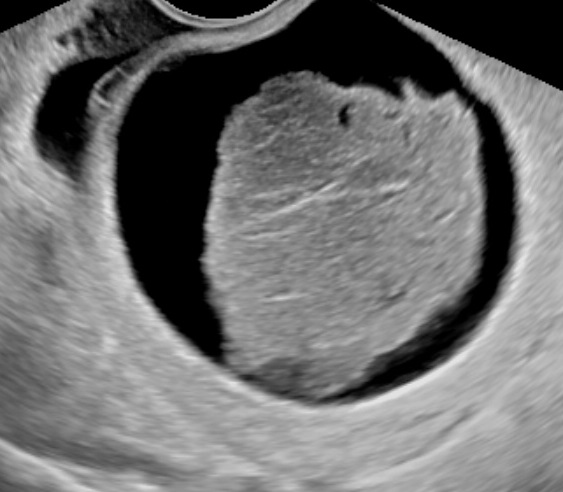

Ovarian Torsion 2